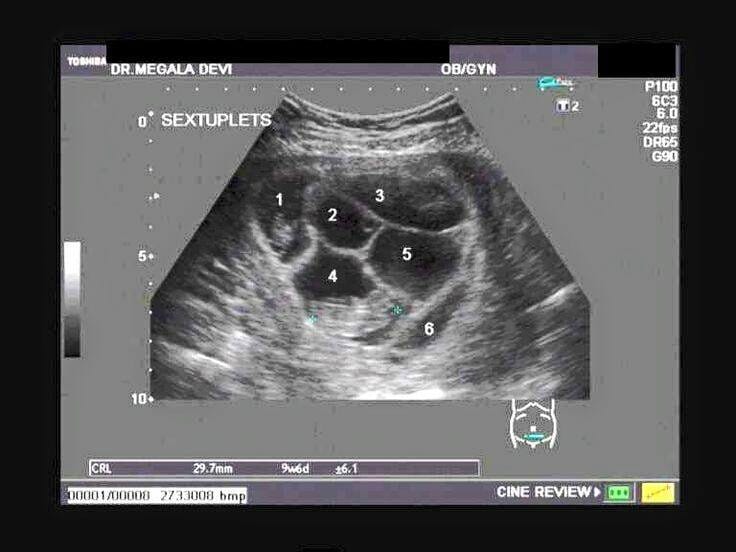

Ultrason sırasında doktor ekrana bakınca şaşırdı ve müjdeli haberi verdi.

Doktor, ‘Burada beş bebek görünüyor” dedi.

Ardından doktor, “Bir dakika! Altıncı bebeği de gördüm!” deyince iyice şok oldular.

Şaşıran çift ekrana bakınca gerçekten de altı bebek olduğunu gördü.